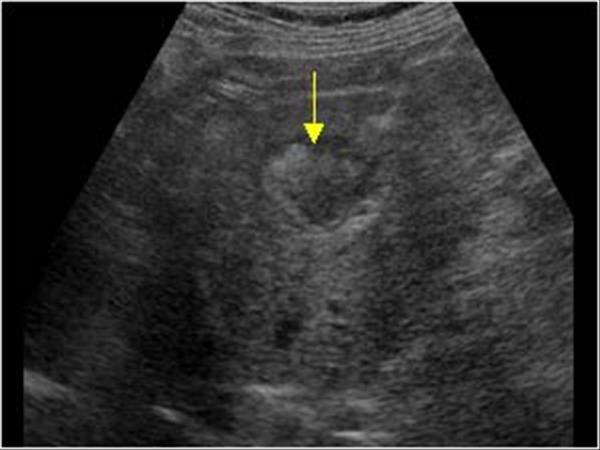

What is Portal Venous Thrombosis?

Portal Venous Thrombosis

What is the sonographic appearance of Portal Venous Thrombosis?

Portal flow absence

echogenic thrombosis

Worm-like

structures near porta hepatis